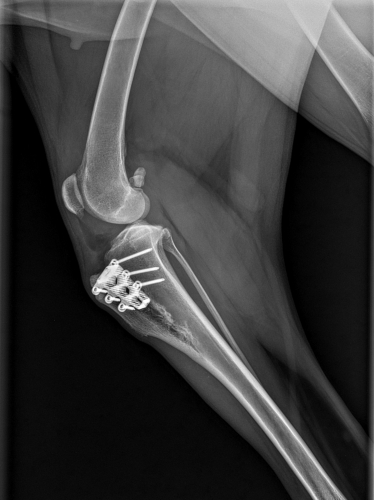

Heute Kontrolluntersuchung zur vollsten Zufriedenheit unserer Tierärztin absolviert. Wenn man das Röntgenbild sieht, wird sofort klar, warum nun für 6 Wochen kurze Leine verordnet ist. Da muß so einiges zusammenwachsen und ausheilen. Der Knochen wurde gespalten und langsam aufgedehnt, damit die Patellarsehne das Kreuzband ersetzen kann, und das Teil, welches fast aussieht, wie eine Haarspange, wurde dazwischen gesetzt. Der Plan ist, daß der Spalt bald wieder zu wächst.

Das Kreuzband wurde repariert, der Meniskus entfernt. Für die nächste Zeit lesen wir folgende Instruktionen: „6 Wochen Ruhe – kurze Leine – kein Toben, auch nicht zu Hause oder im Garten“. Bekümmert schaut sie aber schon drein, weil ihr geliebtes Sofa unzugänglich ist...